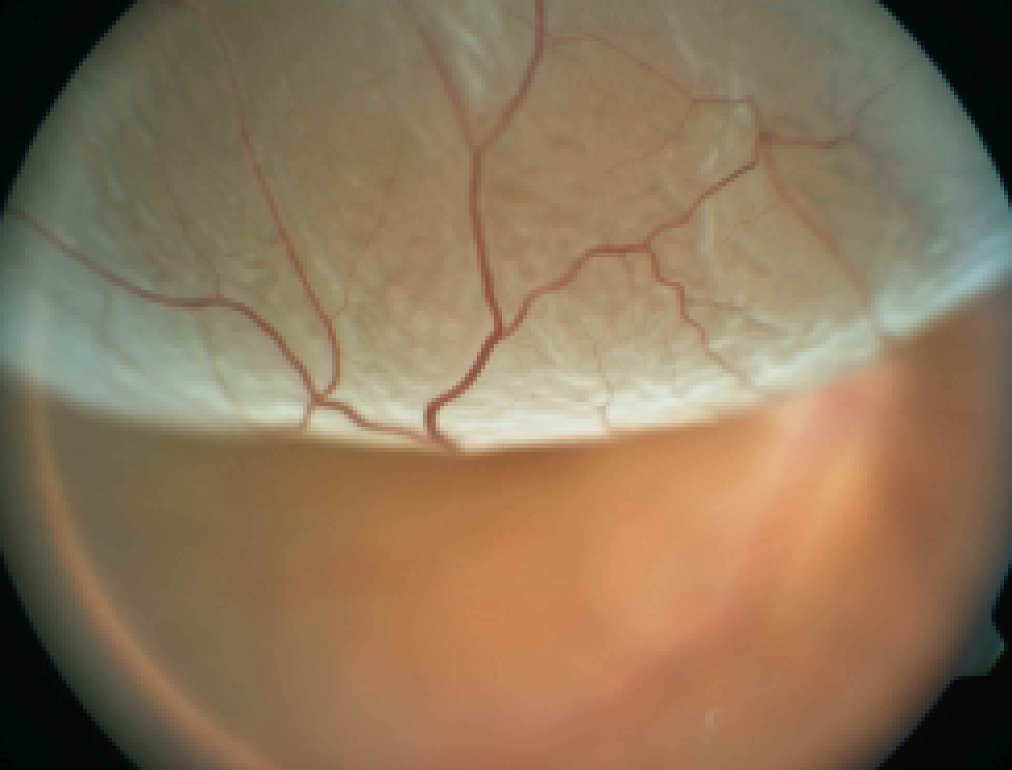

Retinal Detachment